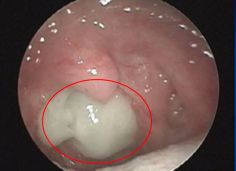

我们查体的时候可以发现,轻轻压舌根时,能够看到白色略发黄的分泌物像瀑布一样悬挂在咽后壁上方,咽后壁淋巴滤泡也明显增生,而双肺听诊的时候却一点异常都没有。这种咳嗽有时甚至都可以达到一个月。孩子家长曾经也在别的医院给其查过几次肺功能,也都没有异常。

图1、咽后壁可以看到黄白色分泌物附着